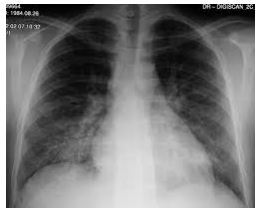

Julio, 52 anos, pardo, advogado, natural de Vila Velha, foi internado com PA: 70/40mmHg, RC3T(rítmo de galope) FC: 120bpm, creptações pulmonares bilaterais. Tempo de reenchimento capilar de 5s. Palidez cutaneo mucosa e sudorese fria. Aos 42 anos de idade apresentou dor precordial prolongada e foi internado com diagnóstico de infarto agudo do miocárdio. Relata ainda hipertensão arterial, diabetes e insuficiência renal crônica.

Choque cardiogênico com edema pulmonar associado (visto pela radiografia), devido ao infarto agudo do miocárdio.